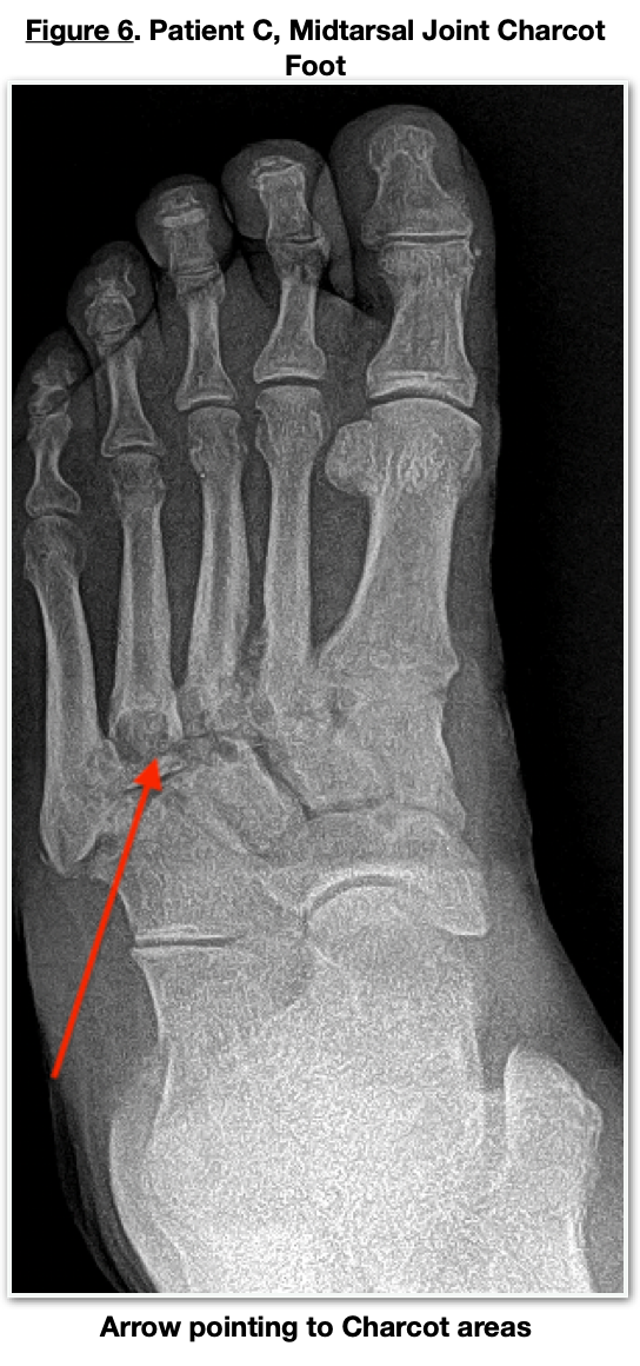

Patient B is a 55-year-old female with a BMI of 40. Her past medical history included diabetes, hypertension, chronic kidney disease (Stage V), end-stage renal disease on dialysis, degenerative joint disease, retinopathy, secondary hyperparathyroidism, and obesity. Medications included rosuvastatin, sertraline, toujeo insulin, auryexia, ferric citrate, furosemide, calcitriol, ezetimibe, vitamin D, and lisinopril. Her HbA1c was 8.7, hematocrit 44%, hemoglobin 13 g/dL, creatinine 3.66 mg/dL, BUN 54 mg/dL, Vitamin D 21 ng/mL, parathyroid hormone 785 ng/L, and C-reactive protein 35 mg/dL. She had been initially immobilized in a CAM boot which was unsuccessful in managing the acute Charcot process. X-rays (Figure 3) revealed subtalar joint collapse, talonavicular joint collapse, anterior calcaneal body fracture, and slight joint depression fracture of the calcaneal body.